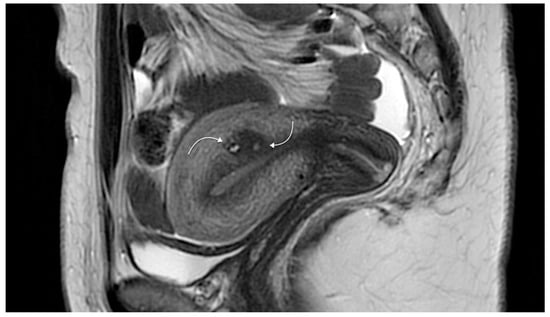

- Uterine cystic adenomyosis